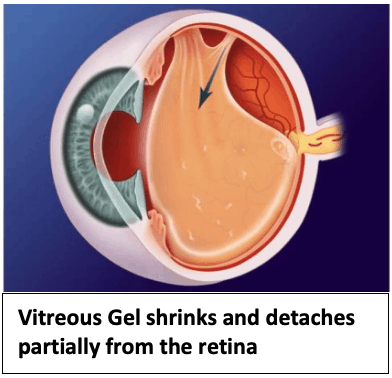

- The vitreous gel shrinks and also changes from being gel-like to being more watery and stringy over time.This causes the formation of strands which cast tiny shadow on the retina which we see as floaters.

- The vitreous gel is also attached to the retina initially. However, as it shrinks, it pulls away and detaches from the retina.

- This may not occur completely, leaving parts of the vitreous gel still attached to parts of the retina.

- When the attached parts of the vitreous gel pulls on the retina, we notice flashes in our eye. These flashes are not caused by stimulation from light entering the eye, but do to mechanical pull by the vitreous gel on the retina. Hence, flashes can occur in the dark without any surrounding light.